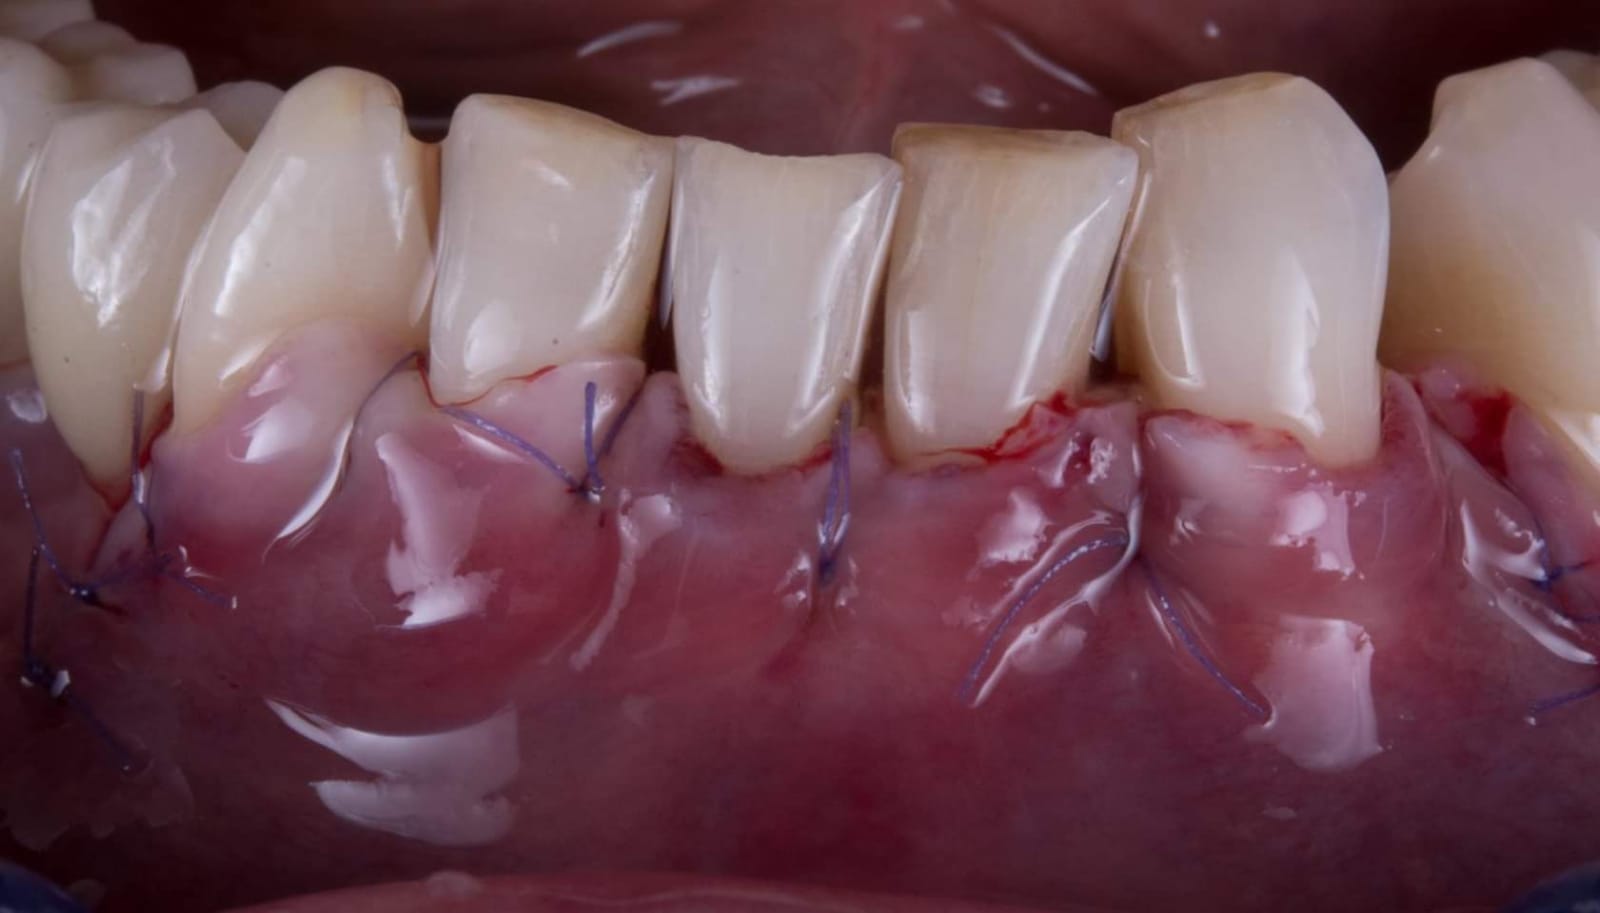

Questa la foto della chirurgia